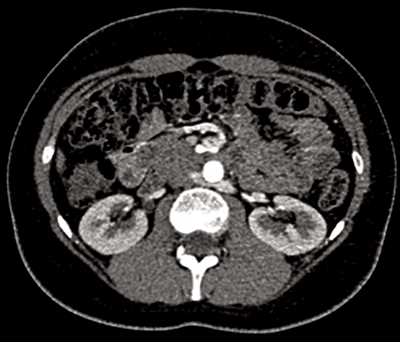

Figure 2: 3D reconstruction of a CTA showing two left renal arteries and three right renal arteries.

Accessory renal arteries (Figure 2)

Unilateral accessory renal arteries can be seen in approximately 30% of patients, with bilateral accessory arteries in approximately 10%, making it the most common renal arterial variation. The common origin for accessory arteries is the aorta or common iliacs between the levels of T11-L4. More rarely the origin may be the lower thoracic aorta, lumbar or mesenteric arteries [4]. Typically the accessory artery passes into the renal hilum and perfuses either the upper or lower renal poles. These hilar accessory arteries are similar in diameter to the main renal artery. However a further subtype exists where the accessory renal artery may enter directly into the renal parenchyma directly from the cortex, commonly at the renal pole; these accessory renal arteries are given the nomenclature polar arteries.

They have the same variety of origin as the hilar accessory renal arteries, but also differ in that the polar arteries have a smaller calibre [2]. The most common accessory artery is a polar artery originating from the aorta, near the main renal artery, and supplying the inferior renal pole. It is important to note that some authors give the nomenclature polar arteries if the vessel enters at the renal pole, irrespective of origin, i.e. the ‘polar artery’ may be an aberrant branch of the main renal artery, and not an accessory artery at all. Regardless of this nomenclature overlap it is important to identify polar arteries as they provide a segmental arterial supply, and if damaged can cause arterial bleeding and, or indeed also renal infarction [1].